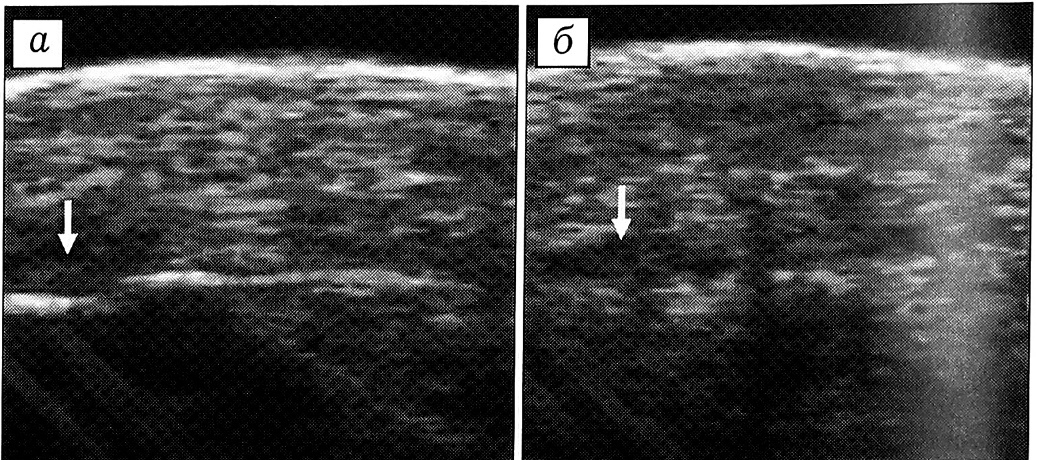

Застарелые повреждения. При застарелых повреждениях сухожилия его концы были или утолщены вследствие рубцового процесса, или, напротив, истончены в результате образования регенерата. Дифференцированная волокнистая структура сухожилия была нарушена, а его эхо-плотность изменена за счет рубцовых, дегенеративных процессов или развития тендинита. Спаечный процесс приводил к нечеткости контуров сухожилия и отсутствию подвижности его концов при динамическом исследовании (рис. 3, а).

В окружающих поврежденное сухожилие мягких тканях обнаруживались более глубокие изменения. По мере организации гематомы места скопления излившейся крови приобретали большую гетерогенность, внутри них образовывались эхоплотные «тяжи» неправильной формы, их контур становился более четким и ровным, эффект «засветления» сохранялся. В результате хронического воспалительного или дистрофического процесса повышалась эхоплотность мягких тканей. Разрастание рубцовой ткани приводило к появлению дополнительных эхоструктур (рис. 3, б).

Рис. 3. Поперечные сонограммы сухожилий сгибателей на уровне срединной ладонной складки через 4 мес после травмы. а — сгибатели III пальца (стрелка): контуры сухожилий нечеткие, структура неоднородная, определяется мозаичная эхогенность — признаки тендинита и спаечного процесса; б — сухожилия сгибателей IV пальца отсутствуют (стрелка).

Осложнения повреждений. Развитие спаечного процесса вызывало более глубокое нарушение дифференцированной волокнистой структуры сухожилия, повышение его эхоплотности. Контуры сухожилия становились нечеткими, в окружающих тканях появлялись дополнительные эхоструктуры (рис. 3, а и рис. 5). При динамическом исследовании отмечалось уменьшение подвижности сухожилия или ее отсутствие. В случае резко выраженного спаечного процесса сухожилие было неотличимо от окружающих мягких тканей — определялся единый высокоэхогенный конгломерат недифференцированной структуры. Границы распространения спаечного процесса выявляли путем исследования различных срезов. При тендините отмечались утолщение сухожилия, нарушение его дифференцированной волокнистой структуры, мозаичная эхогенность (см. рис. 3, а). Теносиновит характеризовался появлением в прилежащем к сухожилию участке зоны однородной структуры резко пониженной эхогенности с четкими краями, которая соответствовала расположенной в синовиальном влагалище полости, заполненной жидкостью (рис. 6). Дистрофические изменения сухожилия сопровождались уменьшением его диаметра, исчезновением дифференцированной волокнистой структуры и образованием аномальных областей повышенной эхогенности (см. рис. 6). При развитии паратенонита сухожилие было утолщено за счет паратенона, его эхографическая структура не изменялась.